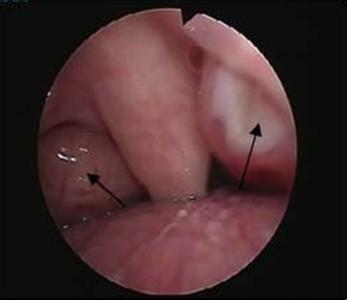

扁桃体炎

扁桃体炎的症状